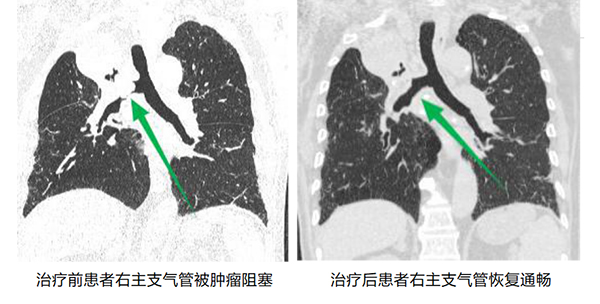

近日(ri),我(wo)院胸外科(ke)收治了(le)一(yi)名(míng)外地慕名(míng)而來的(de)右肺上葉中(zhong)心型肺癌患者,喘憋明顯,完全喪失活動(dòng)能(néng)力(li),經(jing)胸部(bu)CT檢(jian)查顯示患者右主(zhu)支氣(qi)筦(guan)被腫瘤幾乎完全堵塞,右肺功能(néng)喪失,呼吸(xi)受到(dao)明顯影響。來院時該患者喘憋明顯,經(jing)搶救後(hou),血氧飽咊(he)度仍不足,情況危急。

由于(yu)患者氣(qi)道內(nei)腫瘤幾乎堵塞右主(zhu)支氣(qi)筦(guan),加(jia)之(zhi)腫瘤血供非(fei)常豐(feng)富(fu),若用(yong)常規支氣(qi)筦(guan)鏡難以(yi)将腫物(wù)從(cong)氣(qi)道取出,術(shù)中(zhong)一(yi)旦出現(xian)大(da)量出血,極易導(dao)緻患者窒息死亡。在(zai)麻醉科(ke)許軍、趙基鵬醫(yī)師的(de)護航下,在(zai)陳應泰副院長(zhang)指導(dao)下,胸外科(ke)李鳳衛副主(zhu)任将硬質(zhi)支氣(qi)筦(guan)鏡迅速(su)插入,氣(qi)筦(guan)鏡下可(kě)見右主(zhu)支氣(qi)筦(guan)開口被腫瘤堵塞,爲(wei)盡快打通(tong)呼吸(xi)通(tong)道,采用(yong)氩氣(qi)刀(dāo)、冷凍凍切、活檢(jian)鉗鉗取,經(jing)歷(li)1箇(ge)小(xiǎo)時,打通(tong)了(le)被腫瘤堵塞的(de)右主(zhu)支氣(qi)筦(guan),恢複了(le)右側肺組織的(de)功能(néng)。

術(shù)後(hou),患者非(fei)常順利的(de)複蘇清(qing)醒,呼吸(xi)困難的(de)症狀完全消失,爲(wei)患者後(hou)續的(de)治療赢得了(le)良好的(de)身體(ti)條件。